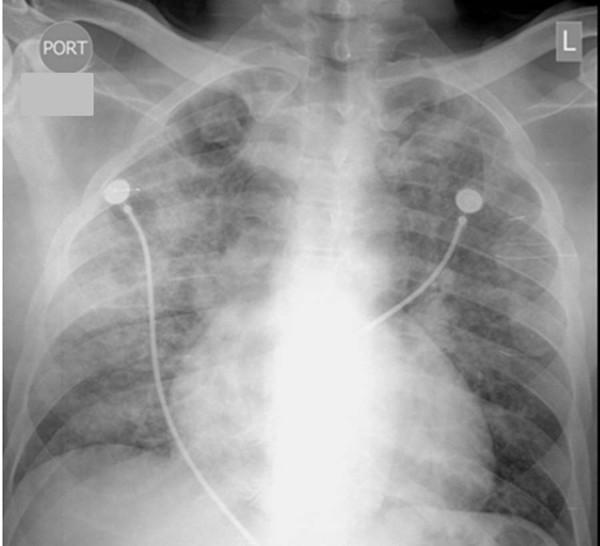

A 42-year-old African American man infected with human immunodeficiency virus was admitted with chronic respiratory symptoms and diffuse pulmonary infiltrates. Chest computed tomography revealed bilateral spontaneous pneumothoraces, for which he required bilateral chest tubes. Initial laboratory investigations did not reveal any contributory conditions. Histological examination of a lung biopsy taken during video-assisted thoracoscopy showed pulmonary alveolar proteinosis concurrent with cytomegalovirus pneumonitis. After ganciclovir treatment, our patient showed radiologic and clinical improvement.

一名42岁感染人类免疫缺陷病毒的非裔美国男性因慢性呼吸道症状和弥漫性肺部浸润入院。胸部计算机断层扫描显示双侧自发性气胸,为此他需要双侧胸腔引流管。初步实验室检查未发现任何相关情况。电视辅助胸腔镜检查期间所取肺活检组织的组织学检查显示肺泡蛋白沉积症合并巨细胞病毒性肺炎。更昔洛韦治疗后,我们的患者在影像学和临床方面均有改善。